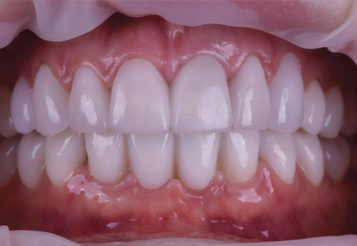

Сразу после операции изготовленный протез фиксируется к имплантам на винты. По завершению операции, можно сразу давать нагрузку на протез. Теперь вы можете есть, говорить и улыбаться совершенно ничего не стесняясь.

Установка протеза

Результаты лечения

Вы получите естественную и привлекательную улыбку

Наши работы

Верните радость улыбки

и уверенность в себе